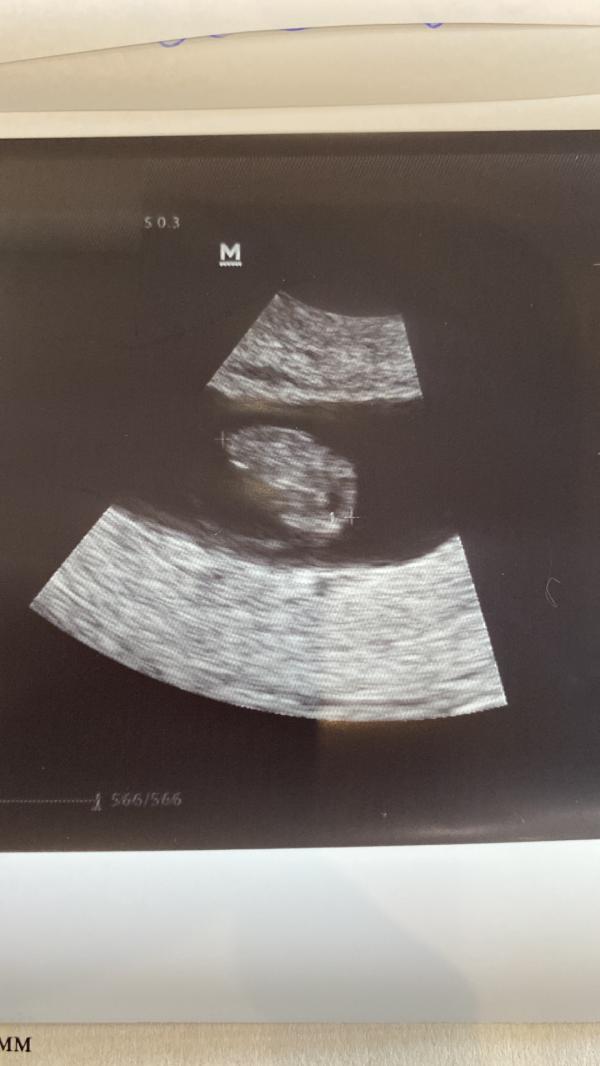

8 недель беременности: как ощущается биение сердца малыша? Мои первые впечатления и эмоции

8 недель моему счастью ❤️❤️❤️ так удивительно видеть, как бьется маленькое сердце